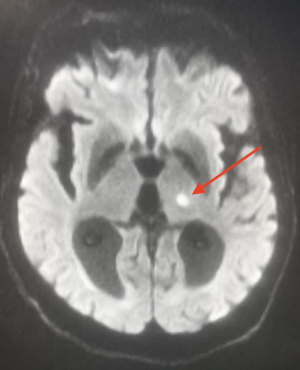

L'IRM reste l'examen de référence et peut révéler :

- Des lacunes récentes : hyper en T2 et en FLAIR.

- Stade aigu : mêmes anomalies de diffusion et ADC que pour les autres types d'AVC (hyper en diffusion et hypo en ADC pour un infarctus)